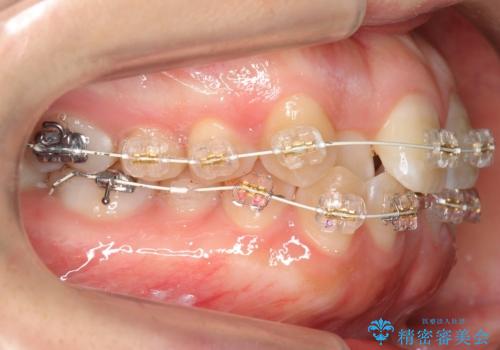

よくある悩み 前歯が裏に2本入っているのを治したい

- 前歯が2本裏に入ってしまっているのを治したいとのことでした。

プラン1:上の正中をずらさない・・・上下左右4本抜歯

プラン2:上の正中は少し左にずれる・・・左の上下2本抜歯

を提案し、プラン2を選択されました。

最小限の抜歯により矯正ができたと、喜んでいただきました。